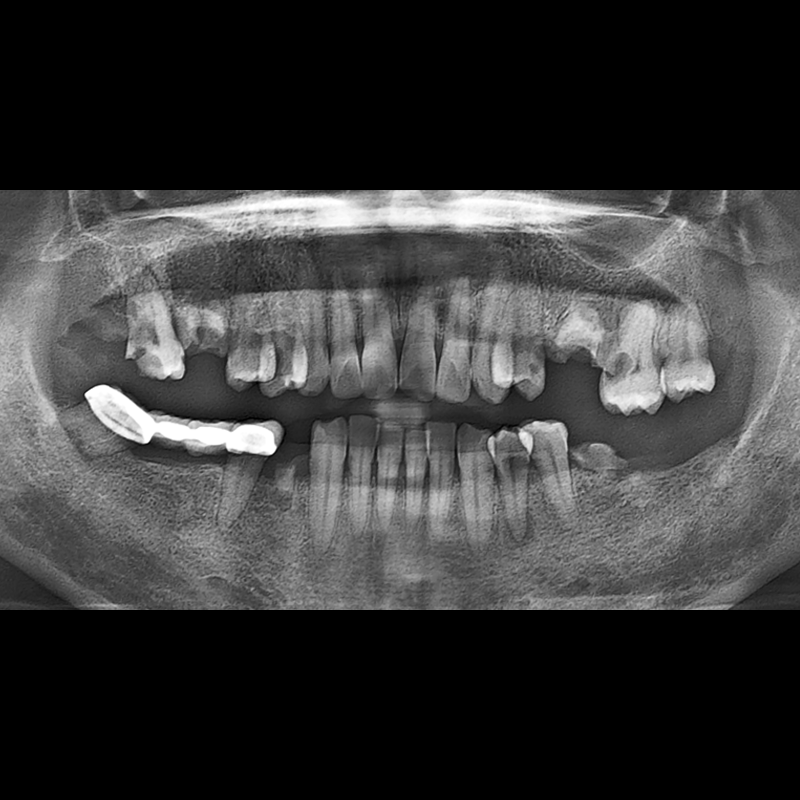

BEFORE AFTER

임플란트 전후사진 2025.12.10

결손된 치아 부분과 살리기 힘든 치아 위치에 임플란트를 식립하였습니다.